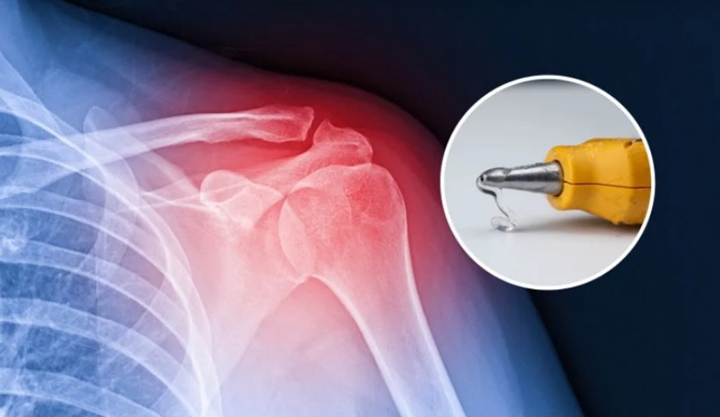

利用3D打印技術(shù)修復(fù)骨骼

科技前沿 37天前

你知道嗎?用于填補(bǔ)骨骼孔洞的醫(yī)用膠水不僅不環(huán)保,而且還可能引發(fā)嚴(yán)重的炎癥風(fēng)險。韓國成均館大學(xué)(SKKU)的研究人員開發(fā)了一種更巧妙的骨骼修復(fù)技術(shù)——利用3D打印技術(shù)。這項技術(shù)需要一種經(jīng)過改進(jìn)的膠槍,能夠在手術(shù)過程中將骨移植物直接打印到活體組織上。